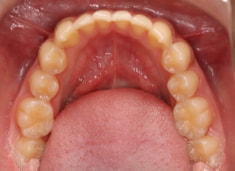

治療前

上下顎のギャップはありますが、顔面自体の幅径は良好な値を示していますので、スペース不足は拡大することによって解決できポテンシャルはあると考えられます。